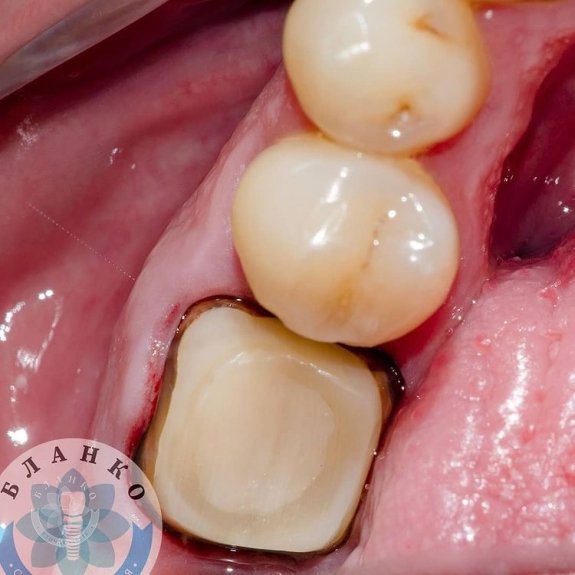

— твердые ткани зуба восстановлены с помощью специального материала

— сняты оттиски и изготовлена высокопрочная, гипоаллергенная и высокоэстетичная коронка из диоксида циркония.